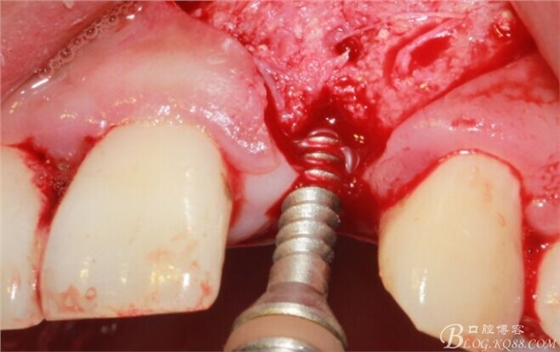

擴(kuò)孔。

骨擠壓。

植入植體。